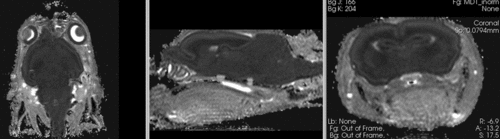

registered brains after 5x5x5 nonrigid BSpline alignment registered brains after 5x5x5 nonrigid BSpline alignment]